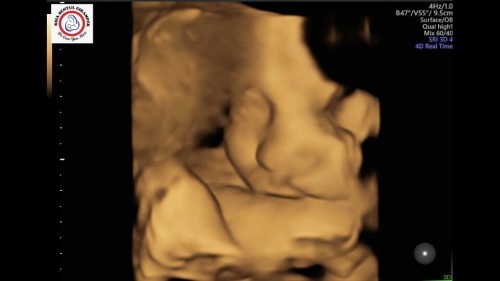

Waktu kandungan 35minggu🥰 dan tiap diusg selalu kaga mau dan manyun” 😘🤣